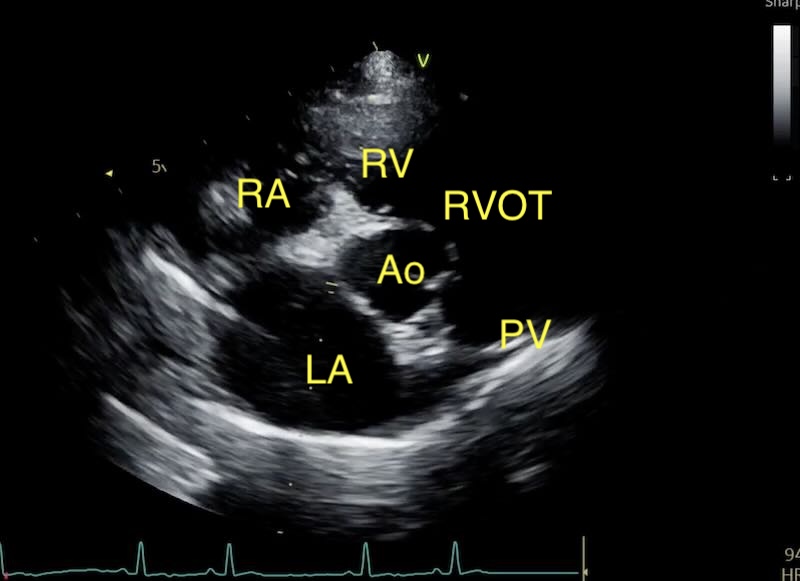

In our first article, we established that left atrial size is really important in veterinary cardiology, and that LA:Ao > 1.6 is the threshold for enlargement, including cats and dogs in defining Stage B2 MMVD and HCM. If cardiology were simple, we would stop there. However, any clinician who has spent time behind a probe knows that the heart base view is rarely perfect, and the “rules” often seem to conflict.

The Invisible Wall: Pulmonary Vein “Dropout”

One of the most frequent challenges in the short-axis view is the “disappearing” posterior wall of the left atrium. The pulmonary veins enter the atrium at its caudolateral aspect, and because the wall here is incredibly thin, it often suffers from ultrasound dropout.

When this happens, the blood in the atrium and the blood in the vein appear to merge into one large anechoic space. If you simply place your caliper at the first visible tissue interface, you will inadvertently include the pulmonary vein in your measurement, leading to an artificially high LA:Ao and a potential misdiagnosis of Stage B2 MMVD.

Here are 2 examples of a normal LA with a pulmonary vein, and a very enlarged LA also having pulmonary vein issues: